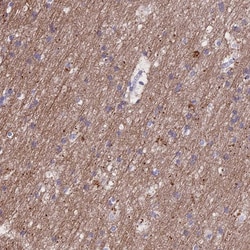

Immunogen sequence: KRTAVRLGDP HFYQDSLWLR KEFMQVRR Highest antigen sequence identity to the following orthologs: Mouse - 96%, Rat - 96%.

| Antigen | TMEM138 |

| Anwendungen | Immunohistochemistry (Paraffin), Western Blot |

| Gen | TMEM138 |

| Gen-Alias | HSPC196; HSPC198; JBTS16; TMEM138; Transmembrane protein 138 |